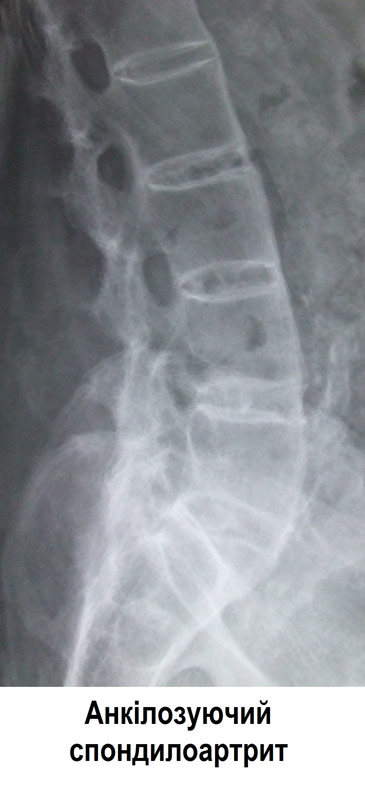

- Рентген чи інші променеві методи діагностики. Рентген дозволить лікарю виявити зміни, що відбулися в суглобах і кістках, хоча характерні наслідки анкілозуючого спондиліту можуть бути і не видимі на початку захворювання. Також можуть бути призначені інші дослідження, такі як комп'ютерна томографія (КТ) або магнітно-резонансна томографія (МРТ), щоб виявити запалення і інші зміни у суглобах.